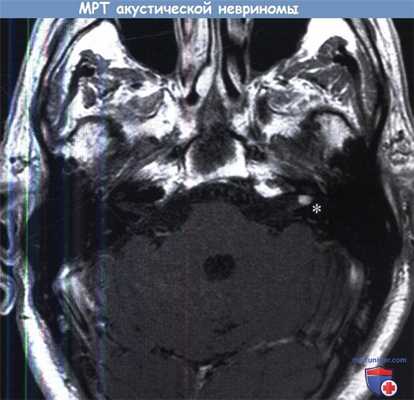

МРТ (Т1 с гадолинием), на которой определяется акустическая невринома левого внутреннего слухового прохода (0,5 см).

При введении контраста сигнал от невриномы усиливается (звездочка).

При введении контраста сигнал от невриномы усиливается (звездочка). Аксиальная МРТ в режиме Т1 с контрастированием. Определяется крупное гиперинтенсивное образование,